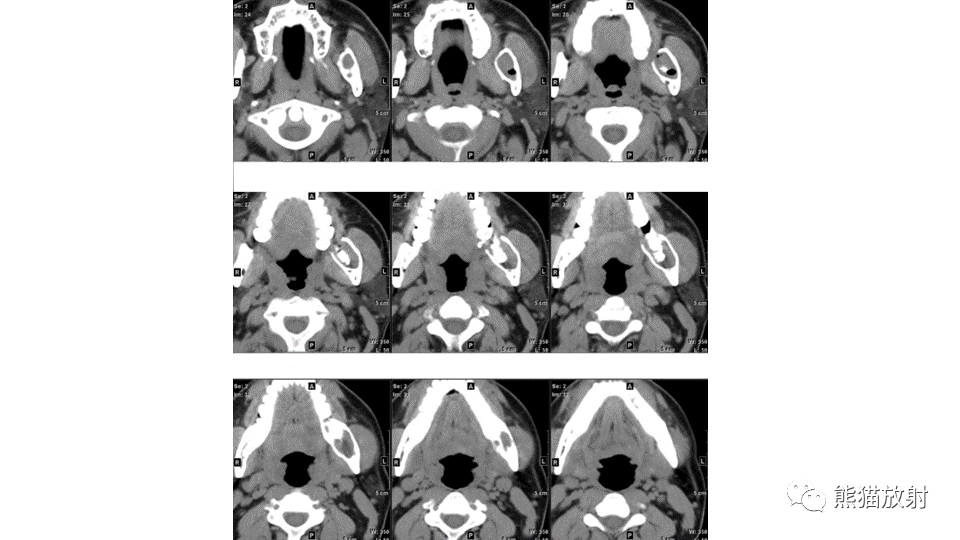

【病例】下颌骨成釉细胞瘤2例CT-13

【病例】下颌骨成釉细胞瘤2例CT-14

【病例】下颌骨成釉细胞瘤2例CT-15

【病例】下颌骨成釉细胞瘤2例CT-16

【病例】下颌骨成釉细胞瘤2例CT-17

【病例】下颌骨成釉细胞瘤2例CT-18